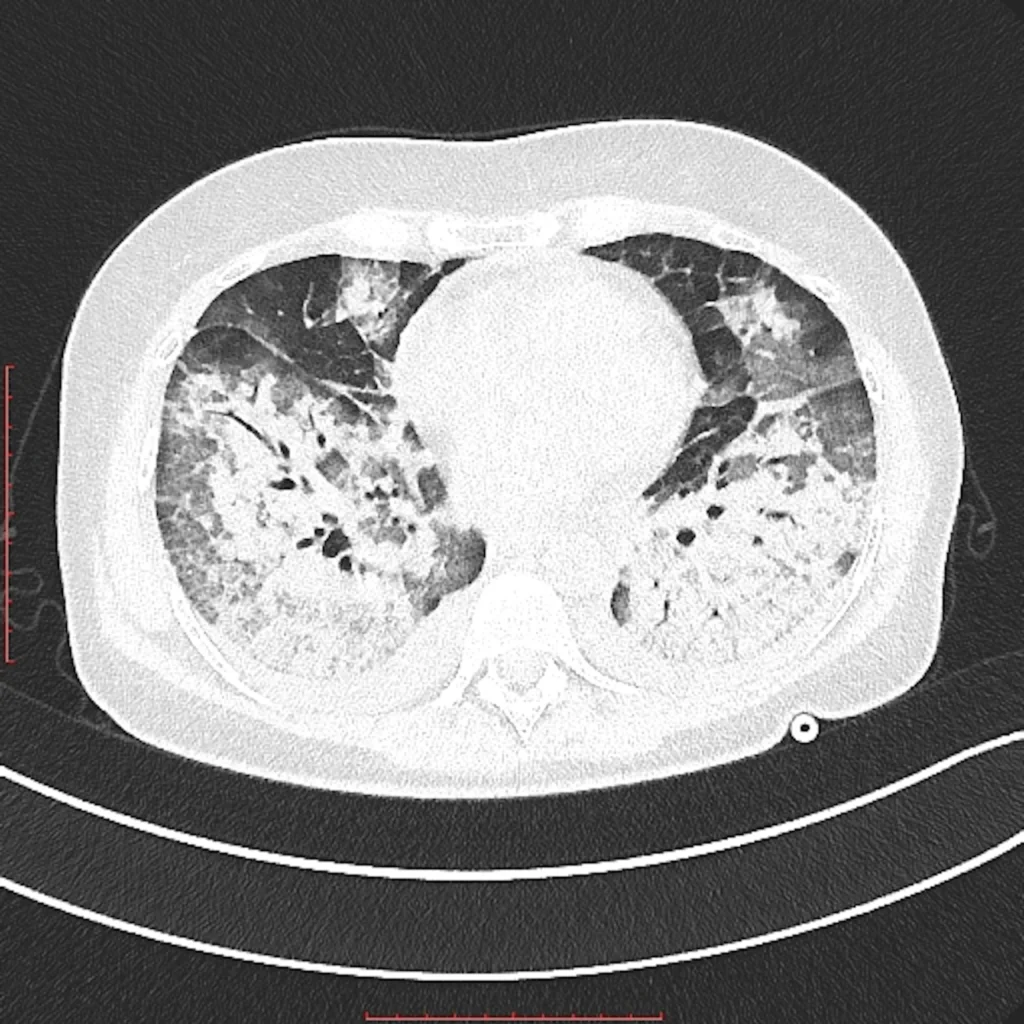

IN SHORT YOUR LUNGS ARE ON FIRE!

Infection of Lungs, which causes cough, shortness of breath, fevers, fluid around lungs, could lead to abscesses in lungs.

Could be caused by bacteria, fungus, virus, mycobacteria and parasites.